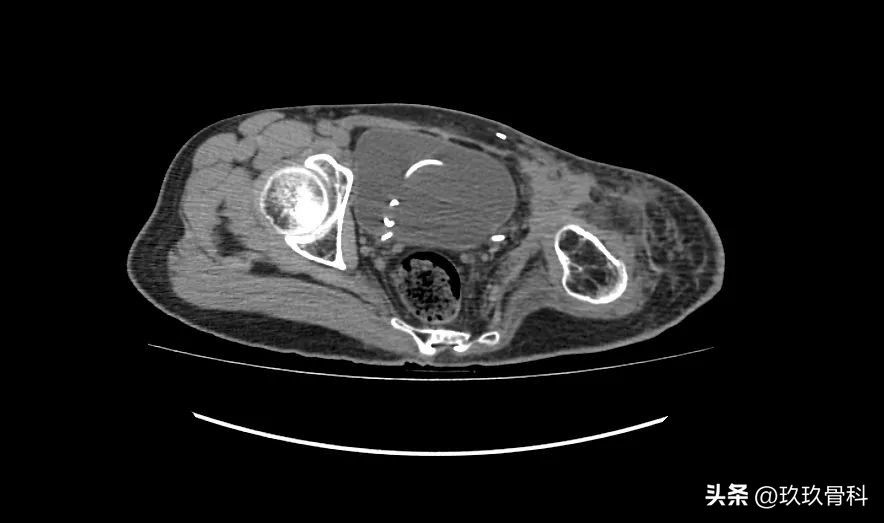

术前影像

2022-08-19 骨盆CT:左侧骨盆术后改变。